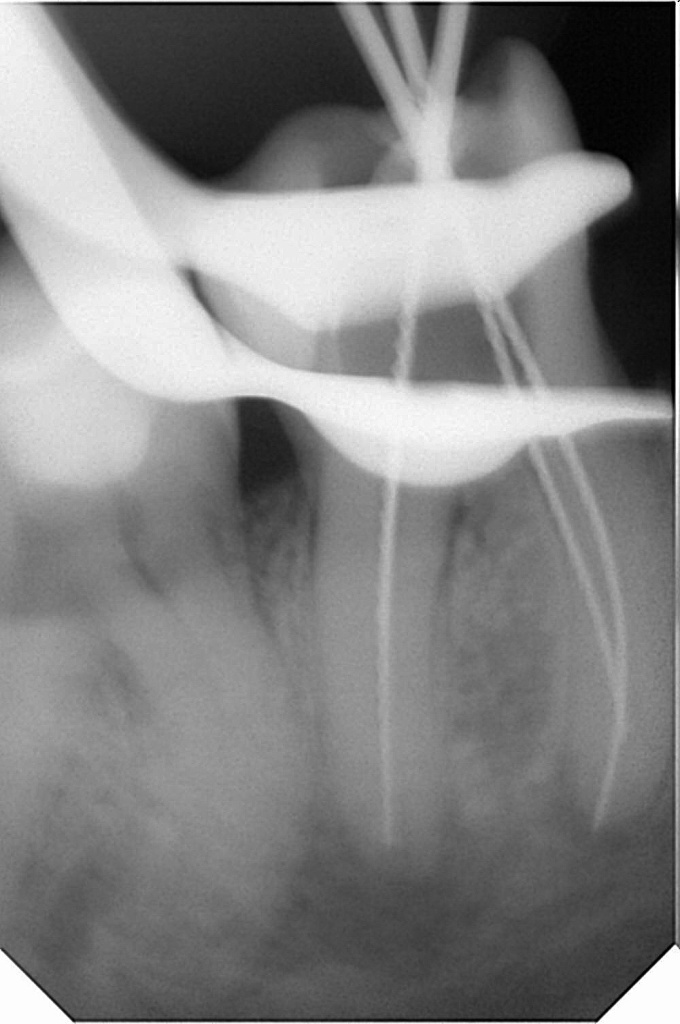

На клинических фотографиях демонстрирующая этапы лечения корневых каналов зуба под микроскопом и с использованием эндомотора.

2. Механическая обработка эндомотором Endo Matic DBA.

Использование машинных файлов с контролем торка и апикального давления.

Эндомотор обеспечивает:

- Автоматическую подачу инструмента.

- Защиту от перегрузки (предотвращение отлома файла).

- Оптимальную скорость работы (например, 300–500 об/мин для вращающихся систем).

4. Контроль качества (фото 3).

- Под микроскопом видна идеально очищенная и сформированная система каналов, готовая к обтурации.

-

Отсутствие остатков дентина, перфораций. На фото 2 показаны полностью распломбированные каналы.

5. Обтурация (фото 4).

Горячая Гуттаперча + силер (термопластический метод вертикальная конденсация ). Более предпочтительный метод обтурации.